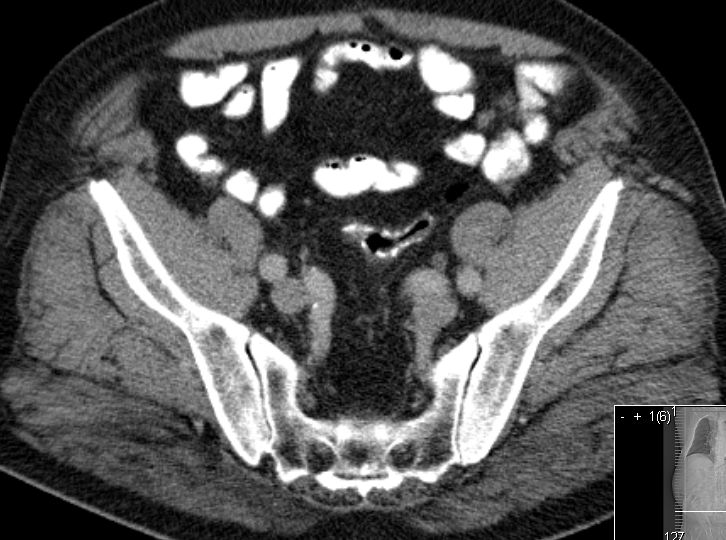

| Ileus | Das CT zeigt einen stenosierenden Sigmatumor mit ausgeprägtem Ileus. |

||

| Metastasen | zahlreiche vergrößerte Lymphknoten paraaortal, paracaval und mesenterial.![]() |